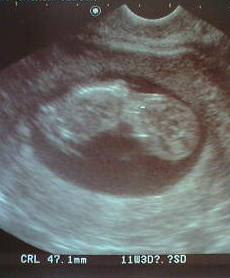

6/17 12週目の検診。

もちろん、モニター画面なんてのもありません。

赤ちゃんの動きが見られないほど、つまらないことはありません(涙)